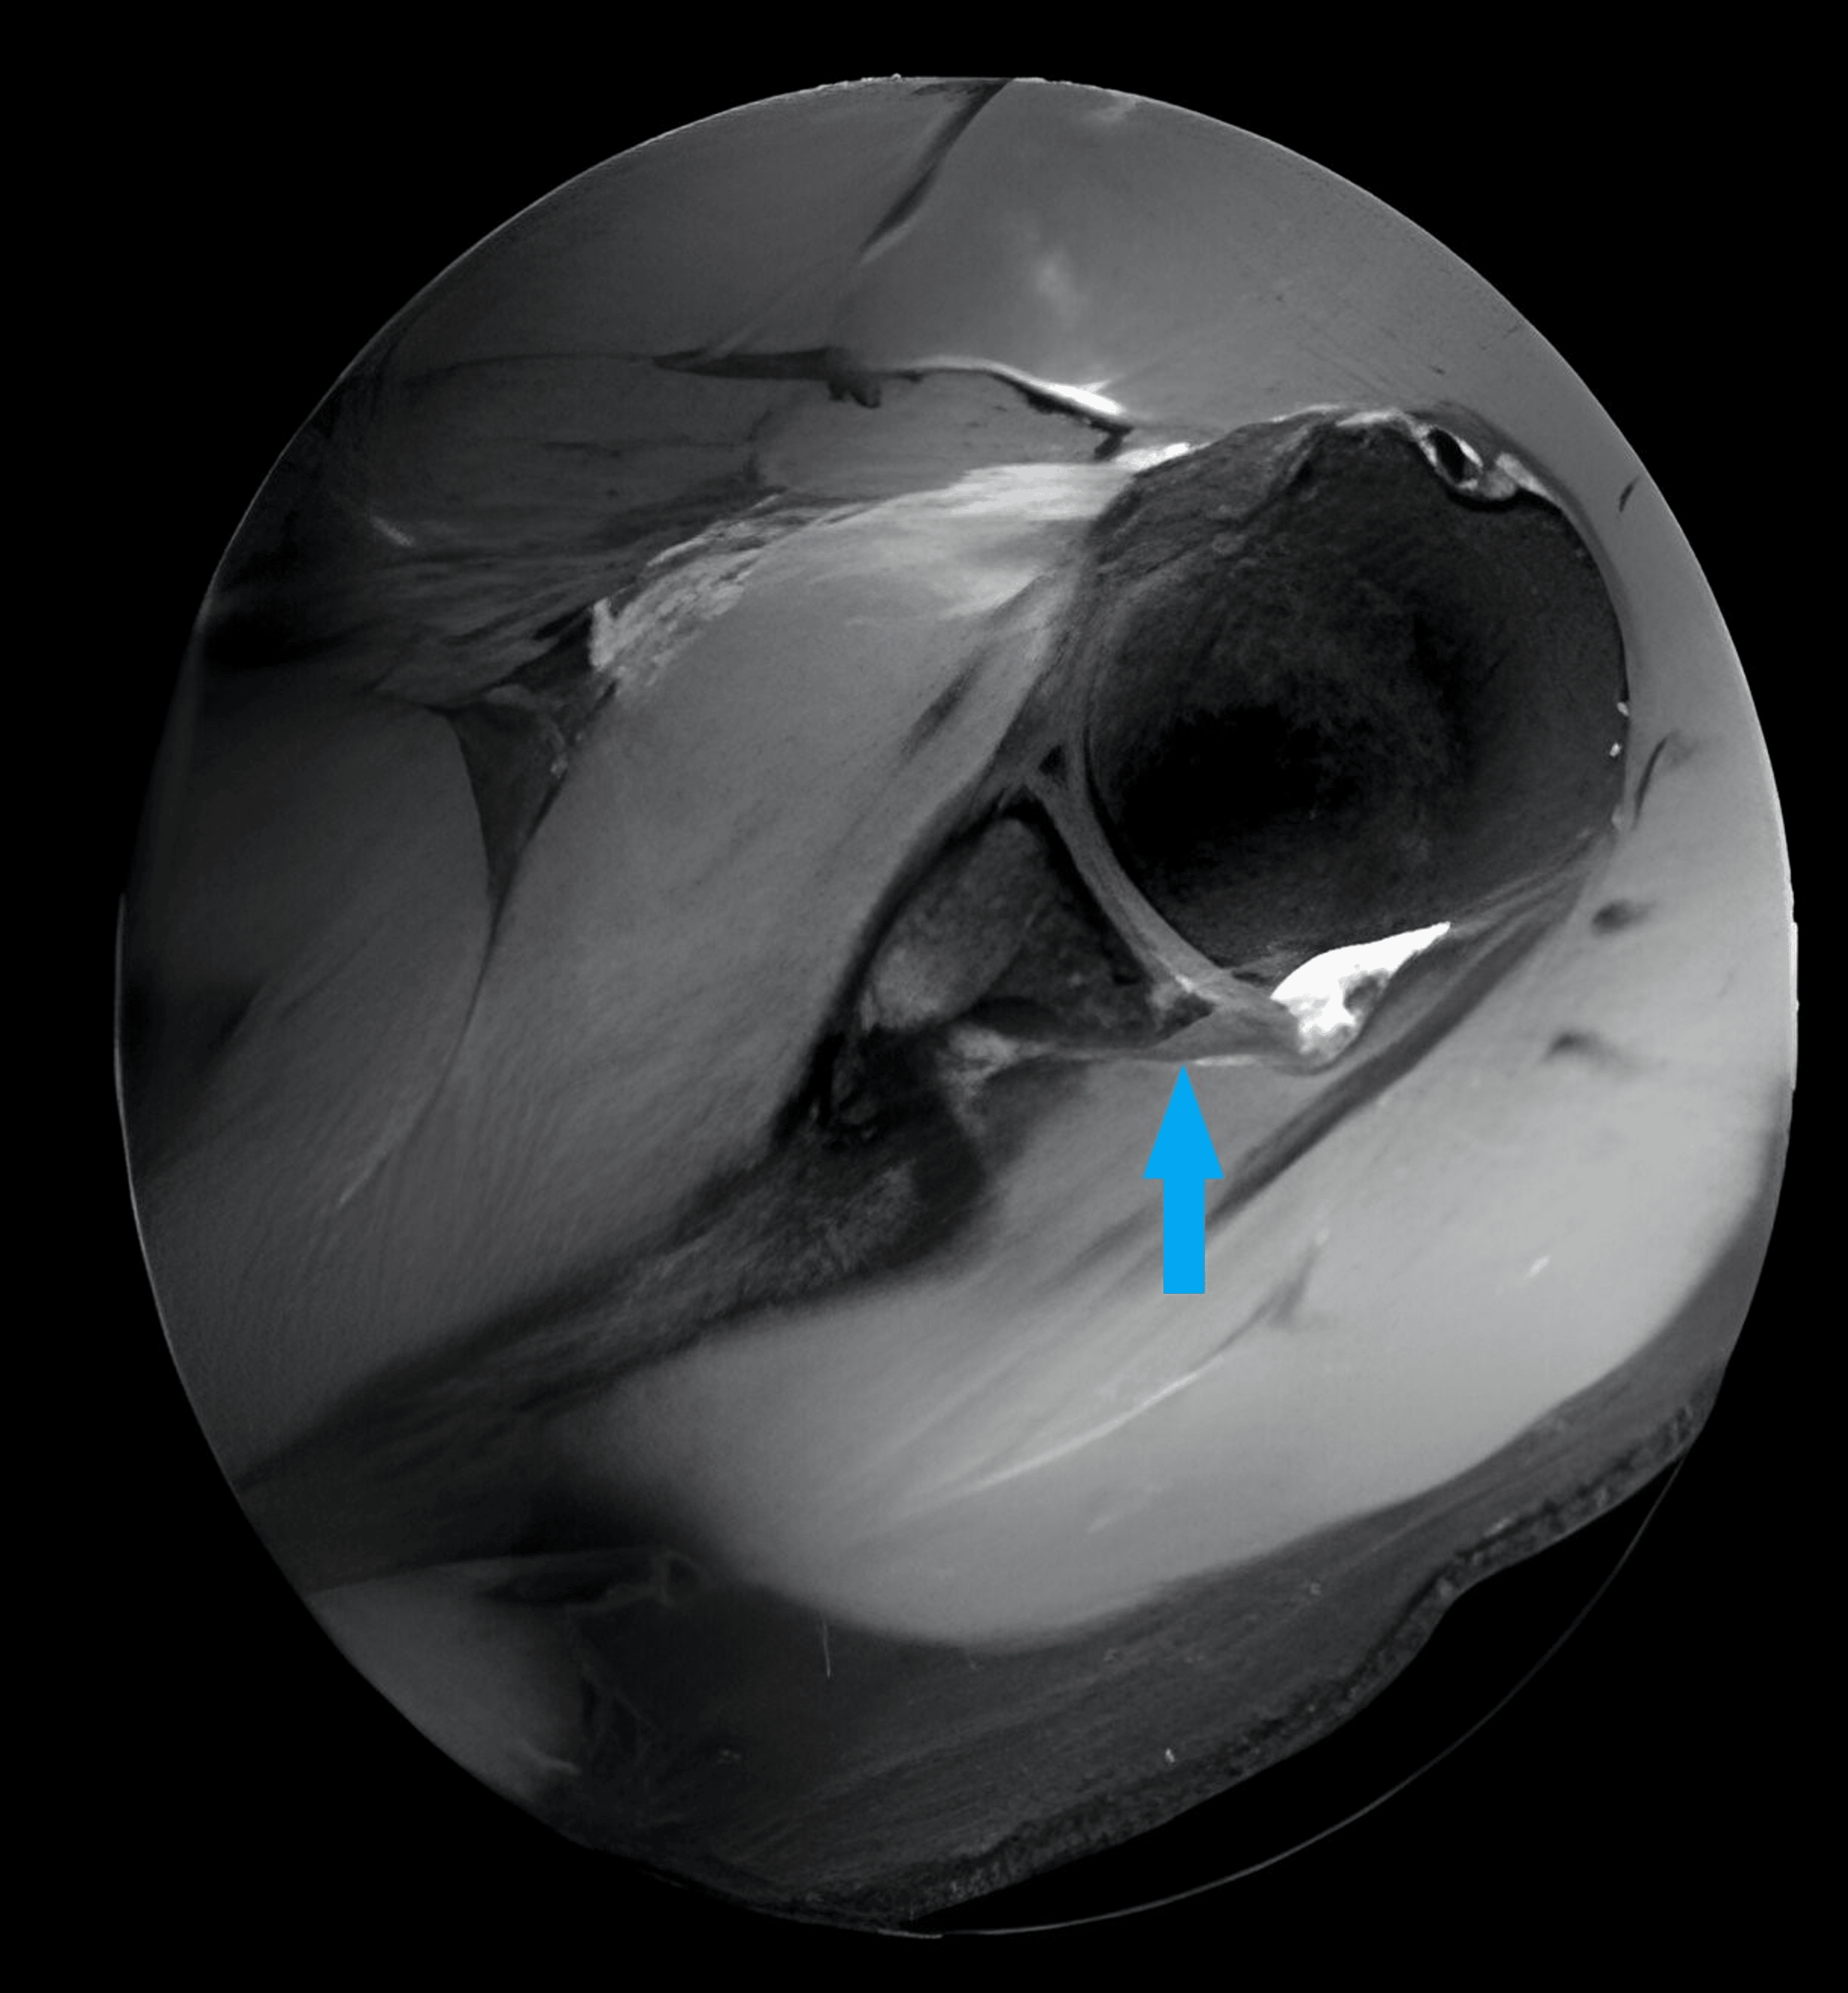

Figure 1 from The Arthroscopic Latarjet Procedure for Anterior Shoulder Open Latarjet Procedure Cpt (1) coracoid exposure and initial release; take the cephalic vein laterally and ligate the large medial branch. i need to make sure i am billing the right cpt for this shoulder surgery: Dissect the interval between the deltoid and the. in this procedure, the provider repairs a tear in the shoulder joint capsule and tightens the joint. Open Latarjet Procedure Cpt.